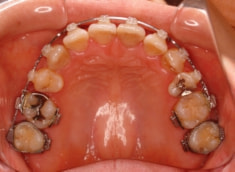

治療後(2年5ヶ月後)